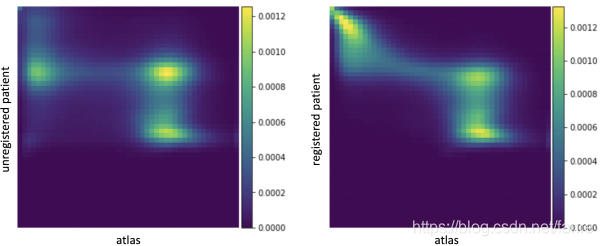

图3.1 描述两幅图像A,B联合分布

图3.1 描述在 bins,两幅图像A,B联合分布

bins,两幅图像A,B联合分布 ,每个在热图中的(i,j)的square表示图像A的强度为i且图像B的强度为j的体素所占的比例,使用上面描述的Parzen窗口近似。左边描述的是还没有配准的两幅图像

,每个在热图中的(i,j)的square表示图像A的强度为i且图像B的强度为j的体素所占的比例,使用上面描述的Parzen窗口近似。左边描述的是还没有配准的两幅图像 分布,右边描述的是使用基于MI损失已经配准好的

分布,右边描述的是使用基于MI损失已经配准好的 分布。直观地看,配准后两幅图像的MI较大,因为热图上的亮点更集中,这意味着一幅图像的体素强度提供了另一幅图像对应体素强度的更多信息。

分布。直观地看,配准后两幅图像的MI较大,因为热图上的亮点更集中,这意味着一幅图像的体素强度提供了另一幅图像对应体素强度的更多信息。